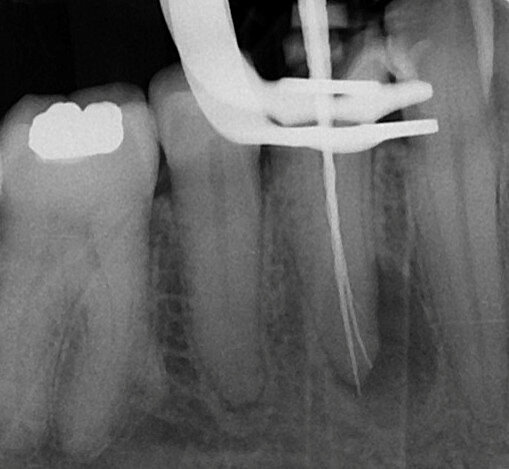

The pulp chamber was opened with a high-speed handpiece and a round bur, and the root canal system rinsed with 5% sodium hypochlorite and then scouted with a prebent ISO size 10 C-PILOT file (VDW). The buccal canal was easily scouted. Orientating the tip of the C-PILOT file lingually, the lingual canal was explored with difficulty and the file came out bent at 10 mm from the tip (Figs. 2 & 3). Preliminary working lengths were immediately established using an apex locator (VDW.CONNECT Locate, VDW) and the C-PILOT file and these were 20.5 and 21.0 mm.

In cases with abrupt curvature in the coronal or middle third, it is recommended to use flexible instruments very resistant to cyclic fatigue. The resistance to cyclic fatigue depends on the alloy used to produce the file and the core of the file. For those reasons, I decided to shape this tooth with the basic sequence of the VDW.ROTATE system (VDW). The blue alloy confers to this file great resistance to cyclic fatigue and permits easy bending of the tip in order to facilitate introduction of the file into an abrupt curvature in the middle third (Fig. 4). The shaping started with the first two files of the basic sequence: the 15.04 and 20.05 were used with a pecking motion in accordance with the manufacturer’s instructions regarding the torque limit and the revolutions per minute. All the shaping was carried out using the VDW.CONNECT Drive (VDW) connected to the apex locator under continuous working length control. In the lingual canal, the files were pre-bent and then introduced manually into the curvature. After that, the file was easily connected to the handpiece thanks to its very small head.